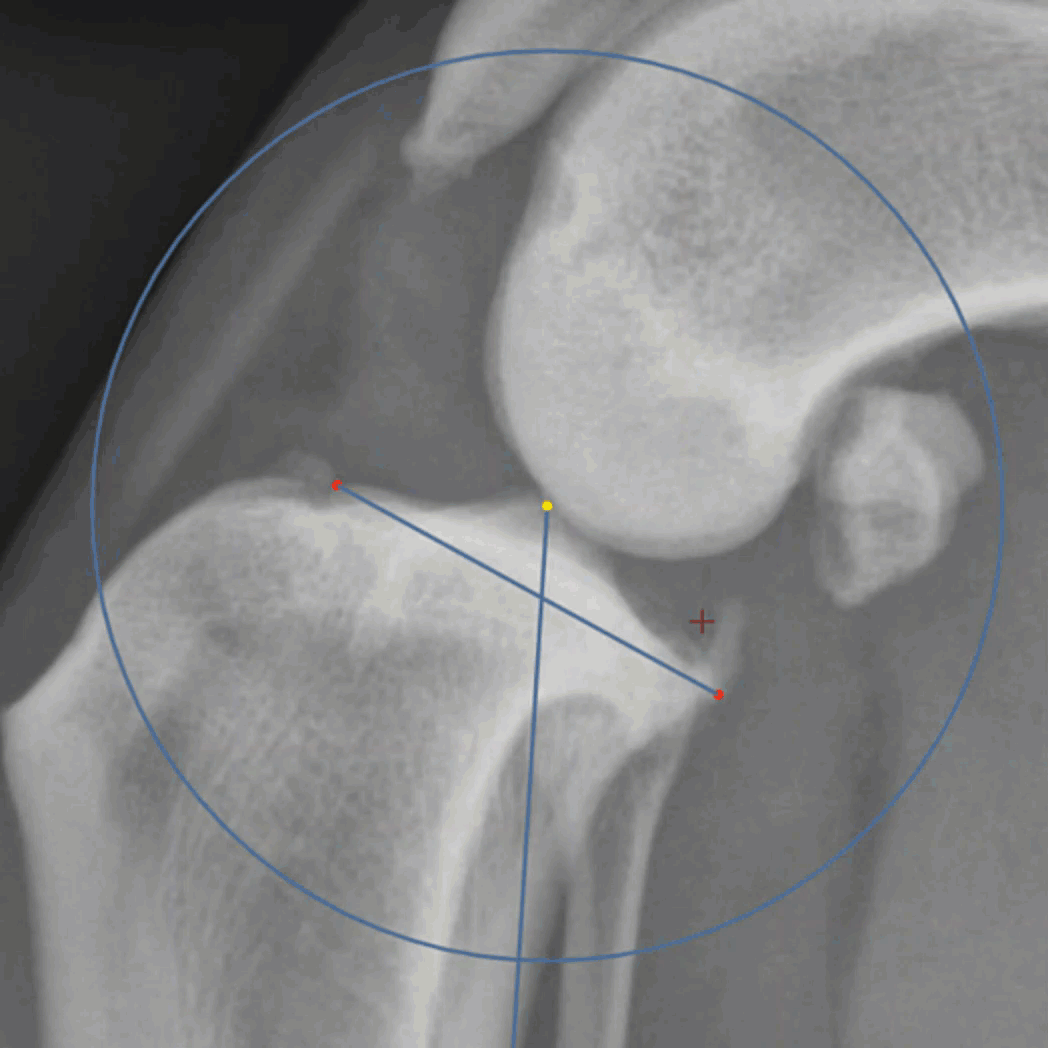

The Manual Polyline cut tool is the traditional method of using the left mouse button to click around the area of interest. Each click will place a grab point around the perimeter of the shape. Since this is a manual process, the user may use approximation with fewer grab points or higher precision with more grab points. To close the shape, click on or near the original grab point.

The center of rotation is the red plus sign that shows in the center of the cut fragment once the shape is complete. The user may click and drag this to define a new location from which the fragment should rotate. When the fragment shape is complete, a label is displayed showing 0 degrees. This will display the rotation and the red grab point is also used to rotate the object around the center of rotation.

Click anywhere within the fragment and drag to move the fragment within the viewport.

Once the fragment has been defined, the purple points along the perimeter are grab points which will allow the user to fine tune the shape of the cut fragment. These can be edited before or after moving or rotating the fragment.